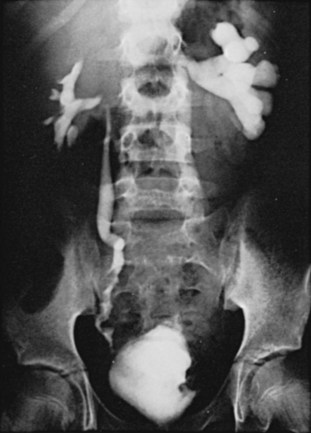

Plain radiographic findings in genitourinary tuberculosis may be seen in the GU tract, surrounding tissues, and up to 50% of patients may show positive findings on chest radiograph. Disparity in renal size on plain films may indicate early increase in size of the affected kidney due to caseous lesions or a shrunken fibrotic kidney of autonephrectomy. Calcifications are seen in 30% to 50% of cases (Roylance et al, 1970). Focal calcifications occur within the caseating lesions (Fig. 16–1). A characteristic diffuse, uniform, extensive parenchymal, putty-like calcification, forming a lobar cast of the kidney is seen with autonephrectomy (Muttarak et al, 2005). Calculi may also be seen in the collecting system or ureter secondary to stricture formation. Ureteral calcifications are rare and are characteristically intraluminal as opposed to the mural calcifications of schistosomiasis. Bladder wall calcifications are not very common except in late cases of bladder contraction. Calcifications of the prostate and seminal vesicles are seen in 10% of cases (Burrill et al, 2007).

Figure 16–1 Kidney-ureter-bladder radiographic view in a patient with left renal tuberculosis with associated calcifications.

The majority of cases will show positive findings on excretory urography, the most common findings being hydrocalycosis, hydronephrosis, or hydroureter due to stricture formation (Wang et al, 2003). Early signs include the moth-eaten appearance of calyceal erosion and papillary irregularity. These signs are best seen on early excretory films, because they are often masked by increasing density of the contrast on later films of the IVU. Cavitary lesions communicating with the collecting system are characteristic of TB. These lesions eventually enlarge as parenchymal destruction ensues, and a picture similar to chronic pyelonephritis may be seen. Fibrotic distortion of the collecting system and ureter is also seen. Calyceal obliteration and amputation, hydrocalycosis, segmental or total hydronephrosis, and a shriveled reduced-capacity renal pelvis may all be signs of renal tuberculosis (Figs. 16-2 and 16-3). Scarring and angulation of the ureteropelvic junction (UPJ) may also occur, the so-called “Kerr’s kink” (Matos et al, 2005). Ultimately diminished or absent function and extensive calcification may be seen with autonephrectomy. If nonvisualized on IVU, the kidney is best evaluated by computed tomography (CT) or ultrasonography.

Tuberculosis of the ureter is commonly seen as a rigid, straightened “pipe-stem” ureter. A beaded, corkscrew appearance is sometimes also seen. Ureterovesical junction obstruction is caused by tuberculous cystitis or strictures of the distal third of the ureter (Fig. 16–4). Secondary stone formation on top of this stricture is an occasional finding. The cystogram films may show a small contracted bladder due to excessive fibrosis (Fig. 16–5). Of note, although IVU is being phased out by CT-urography in many developed countries (Stacul et al, 2008), IVU continues to be a reliable imaging modality for genitourinary TB in most parts of the world.